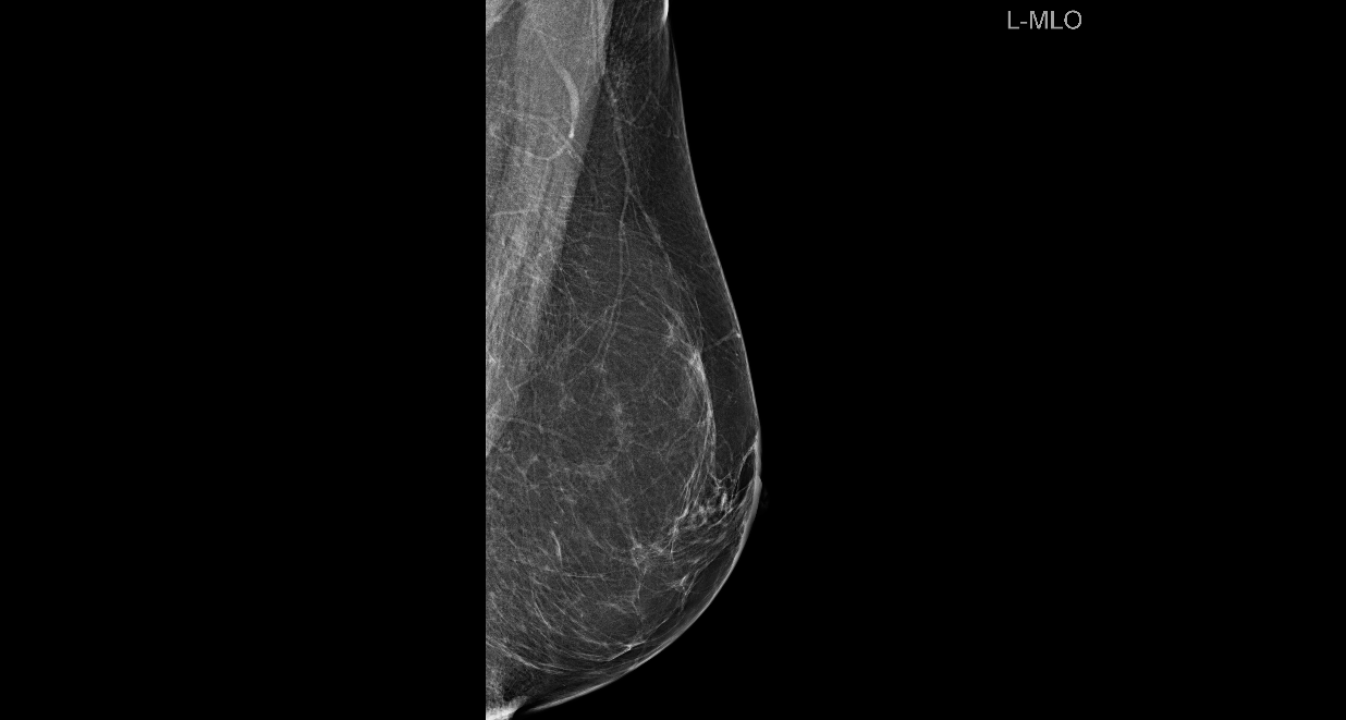

Povodom mjeseca borbe protiv raka dojke

Poliklinika Affidea Vita svojim pacijenticama nudi besplatne preglede dojki!

Listopad je mjesec borbe protiv raka dojke, jedne od najčešće dijagnosticiranih zloćudnih bolesti kod žena.